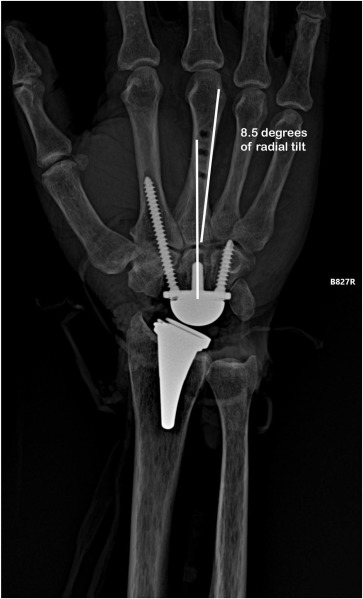

1) Radyal komponent hizalanması; Önkol (radius) anatomik ekseni ile hizalanır

2) Karpal komponent hizalanması; 3. metakarpal (uzun parmak) şaft ekseni ile hizalanır

Kritik nokta: Özellikle ulnar korteks referansı kullanılır. Çünkü Karpal blok doğal olarak hafif ulnar eğilimlidir. Bunun biyomekanik sonucu 3 noktada belirir.

c-İmpingement azalır; Komponentler çarpışmaz. Özellikle radial styloid ulnar tarafta konumlanır.

“Radyal bileşeni önkol ekseniyle, karpal bileşeni uzun parmak metakarpal şaftının ulnar korteksiyle hizalamak…” diğer ifade ile; Radial component → radial shaft axis, Carpal component → 3rd metacarpal axis